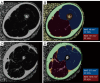

MRI-based quantification on T1-weighted images of the calf in a male patient with HIV-lipodystrophy and metabolic syndrome (A) and a healthy control (B), using Analyze 10.0 software with thresholds for IMAT (red long arrows) and MV (red short arrows). The patient (A) exhibited lower IMAT and higher MV than the healthy control (B). Localized 1-dimensional 1H-MRS using point-resolve spectroscopy data were collected from a voxel within the tibialis anterior muscle on axial T1-weighted image (C). LCModel software was employed to obtain spectra results, revealing that the patient (D) had higher IMCL and EMCL than the healthy control (E) (red arrowheads). EMCL, extramyocellular lipids; IMCL, intramyocellular lipids; SD, standard deviation; MRI, magnetic resonance imaging; IMAT, intermuscular adipose tissue; MV, muscular volume; 1H-MRS, proton magnetic resonance spectroscopy.

Whole-body muscle MRI in a patient with congenital muscular dystrophy (GNE or Nonaka myopathy). Axial (A) and coronal (B) T1-weighted images of various regions reveal a nearly symmetrical bilateral pattern of muscle fatty infiltration grades 3 (30–60%) and 4 (>60%), as assessed by the 5-point modified Mercuri scale, in several muscles of the different levels. MRI, magnetic resonance imaging.